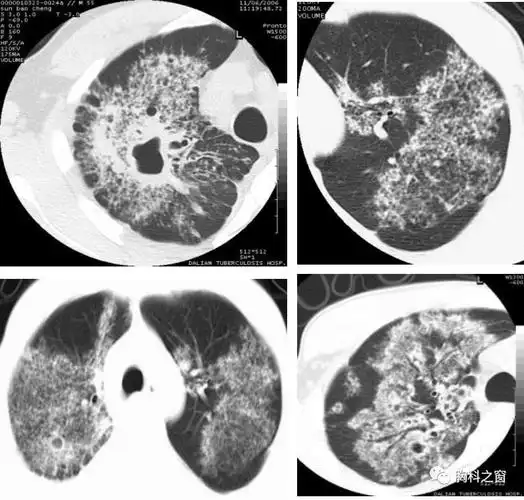

肺结核的薄层ct征象树芽型的病理意义